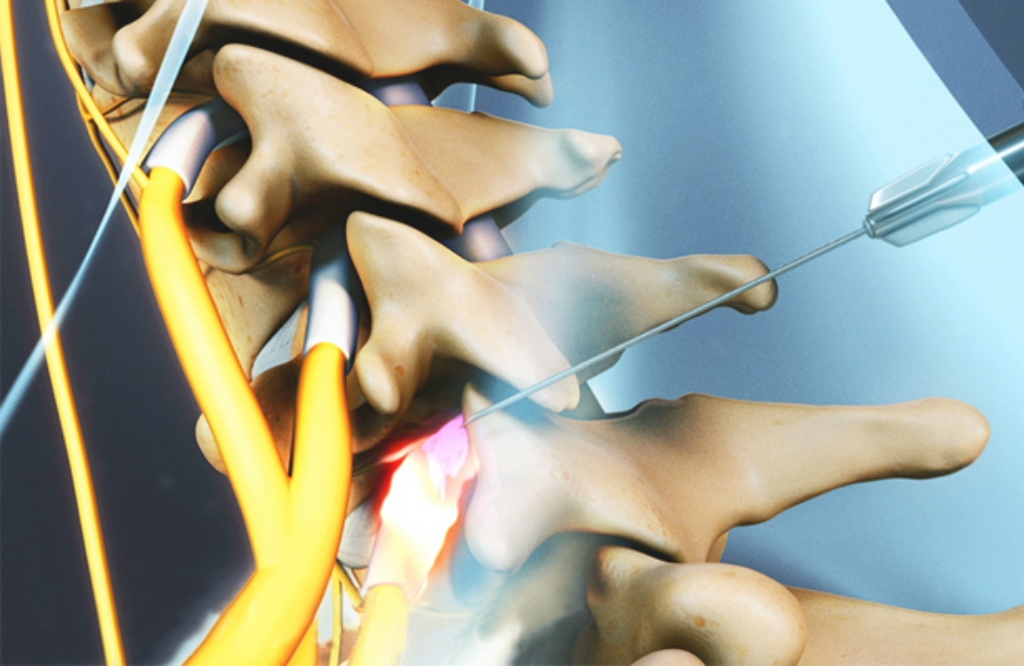

O bloqueio de nervo é um procedimento minimamente invasivo utilizado para o alívio rápido e eficaz da dor crônica. A técnica consiste na aplicação de anestésicos e anti-inflamatórios diretamente nos nervos responsáveis pela dor, reduzindo a sensibilidade da região afetada e proporcionando mais conforto ao paciente.

Essa abordagem é especialmente indicada para pacientes que sofrem com dores na coluna, hérnias de disco, neuralgias, síndrome do túnel do carpo e dores articulares crônicas, condições que comprometem a mobilidade e impactam a qualidade de vida. Com esse tratamento, é possível reduzir o uso de analgésicos, evitar procedimentos cirúrgicos e restaurar o bem-estar.

Os bloqueios são personalizados conforme a necessidade de cada paciente e podem ser utilizados como alternativa para evitar cirurgias ou como parte de um tratamento multidisciplinar. Além disso, os efeitos podem ser duradouros, permitindo um retorno mais rápido às atividades normais.